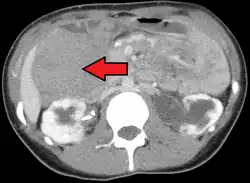

Desmoid tumor as seen on CT scan

Desmoid tumors can occur almost anywhere in the body.[19] They are classified as extra-abdominal, abdominal wall, or intra-abdominal; the last is more common in patients with FAP.[26] Most cases occur in the mesentery, abdominal wall, and extremities.[27] One study has shown extra-abdominal tumors making up 43% of cases, abdominal tumors 49%, and mesenteric 8%, though statistics vary.[16] Pregnancy-related tumors typically arise in the abdominal wall.[28] Tumors located intra-abdominally or in the head and neck have the highest risk of mortality due to the proximity to vital structures.[20]

One analysis has shown a median tumor size of 7.5 cm (3.0 in).[19] Though metastasis cannot occur, the tumors may in some cases be multifocal, with several located in the same body part.[29]